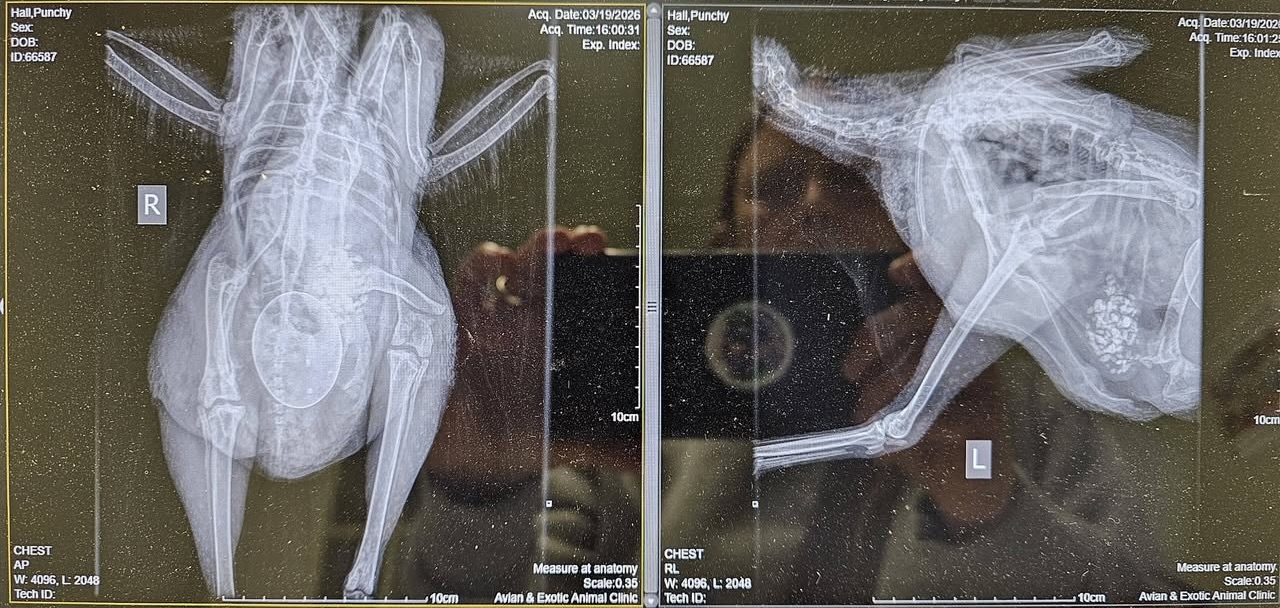

Day 2: I got her into an emergency appointment at the vet. The x-ray looked horrible, with the break very near the knee joint. Additionally the break was complete and a spiral. The prognosis of a good outcome was only 40%. A pin was placed during surgery, but the surgeon was not able to place a stabilizer because of the location and the spiral break. It was imperative that Punchy had to remain immobilized.